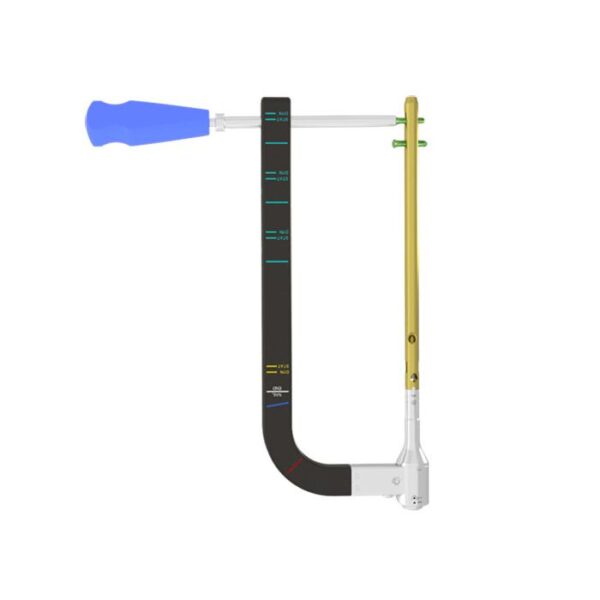

Eje direccional de carbono de cinco dedos:

- Una pieza de eje de puntería que está hecha de material de fibra de carbono garantiza la precisión de bloqueo.

- Simplifique el proceso de operación y acorte el tiempo de operación.